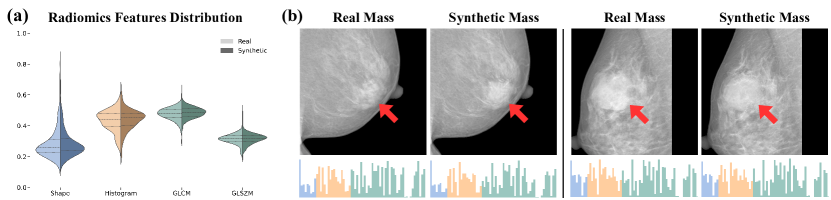

3.1.1 Radiomics Feature Consistency

We assessed RadiomicsFill’s ability to generate tumors reflecting specified radiomics features by comparing the radiomics features of generated tumors against those of the input image in unseen test set conditions. We employed a pretrained nnUNet model [7], trained on the mass training set, to predict synthetic tumor contours from mass images and bounding box mask images. The high similarity observed in Fig. 4 between input and synthetic tumor radiomics features confirms RadiomicsFill’s effectiveness in accurately mirroring the given conditions in tumor generation.

Refer to caption

Figure 4: Radiomics Feature Consistency Between Real and Synthetic Masses. (a) Grouped violin plots for shape, histogram, and texture (GLCM and GLSZM) features, contrasting real (left) and synthetic (right) distributions. (b) Visual comparison of real and synthetic masses, with red arrows highlighting masses and histograms visualizing the 67 extracted radiomics features underneath.